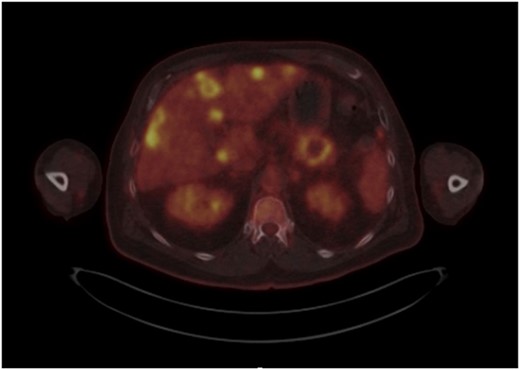

Post-review, he was listed for an urgent biopsy under local anaesthetic. Histology showed well-to-moderately differentiated adenocarcinoma, with the likely primary being upper gastrointestinal or pancreatic in origin. Positive immunostaining was noted for CK7 and negative for p63, TTF-1, Napsin, CK20 and PSA. Magnetic resonance imaging (MRI) of the face and neck showed a 2.6-cm lesion on the chin invading subcutaneous tissues, with no mandibular involvement (Fig. 1). Due to the nature of the histology results, he underwent a positron emission tomography(PET)-computed tomography (CT) scan, which showed a cystic area in the pancreatic tail, alluding to a pancreatic adenocarcinoma primary. Widespread metastases noted included multifocal liver metastases, peritoneal lymph node, muscle and bony involvement (Figs 2–4).